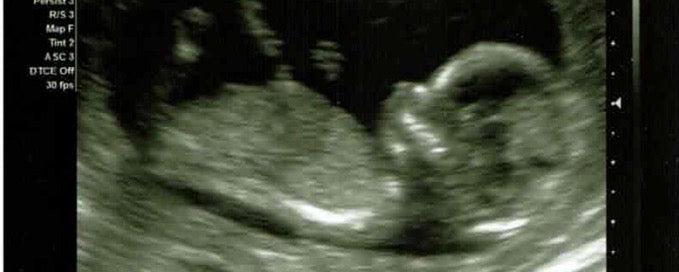

each sonogram made it feel more and more real.

Sunday Jan 13th I was about to do just that for the first time in my life. See I was 18 weeks pregnant and aside from a really bad sinus infection the past few days I was training better than I had my whole pregnancy, but better is relative. Rewind back to Sept; I struggled to train, I struggled so much I wound up at a cardiologist. I had my resting heart rate in the 80s (normally in the 40s) and the inability to do more than a mile without struggling and raising my heart rate up to 20k race pace. And that’s how we found out we were pregnant, through an early blood test to clear me for a CT scan. And as soon as you’re pregnant well it seems like any and every symptom can be attributed to or at least obscured by the physical task of growing another human. The only problem was because of our fertility struggles we knew exactly when we conceived and knew that my symptoms preceded conception by several weeks and thus could not be dismissed due to pregnancy alone. But no answers were reached and instead I went about my life in this weird haze of not really training, knowing physical activity was extremely encouraged for the health of me and my baby, all the while afraid it was all too good to be true and whatever affected me before conception surely wouldn’t allow me to stay pregnant. In fact I was alarmed that if my body was struggling this much physically this early how could it ever make it another 8+ months. But week after week, ultrasound after ultrasound, blood draw after blood draw I was still pregnant and finally after the second time hearing her rapid little heart beat I believed that this blessing was for real.